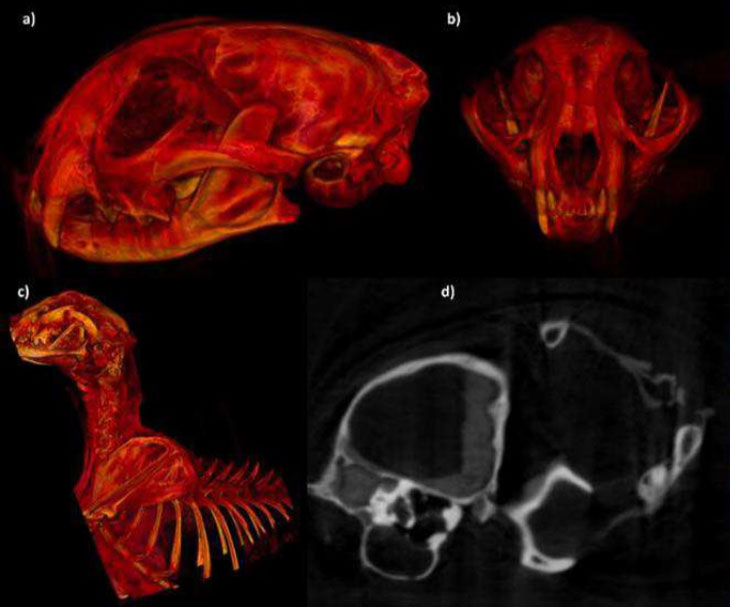

Entre 2022 et 2023, Ahmed Boug, du Centre national pour la faune sauvage à Riyad, et ses collègues ont mis au jour les momies de sept guépards, ainsi que les restes squelettiques de 54 autres, dans les grottes de Lauga. Selon l’équipe, il s’agit des premiers exemples connus de grands félidés momifiés naturellement. Un processus favorisé par des températures stables et de faibles niveaux d’humidité.

L’examen d’une vingtaine de crânes a révélé que six d’entre eux étaient ceux d’individus matures, quand les autres avaient entre 6 et 24 mois au moment de leur mort. Associés à la découverte des ossements de neufs juvéniles, ils suggèrent que le système de grottes constituait un abri pour les femelles et leurs petits.